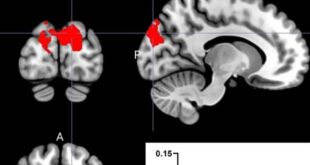

التدخين أثناء الحمل يرفع ضغط الدم لدى الأطفال ويزيد خطر أمراض القلب

كشفت دراسة علمية حديثة أن التدخين أثناء الحمل قد يزيد من خطر ارتفاع ضغط الدم لدى الأطفال، مما قد يرفع احتمالية إصابتهم بأمراض القلب في مراحل لاحقة من الحياة. وتؤكد النتائج أهمية الإقلاع عن التدخين خلال الحمل لحماية صحة الأجيال القادمة. تفاصيل الدراسة والجهات المشاركة أُجريت الدراسة ضمن مشروع ECHO، وهو برنامج …

طريقة تناول البروبيوتيك—كبسولات أم مسحوق—تؤثر بشكل مختلف على الدماغ

أظهرت دراسة جديدة من جامعة أوريبرو Örebro University أن شكل تناول  —سواء كبسولات أو مسحوق—يؤثر البروبيوتيك على كيفية تأثيره على الدماغ. تم نشر الدراسة في مجلة Brain, Behavior, and Immunity Brain, Behavior, and Immunity، وتركز على إمكانيات تخصيص تناول البروبيوتيك وفق أهداف محددة، مثل تحسين الذاكرة أو دعم الصحة النفسية. البروبيوتيك وصحة الدماغ …